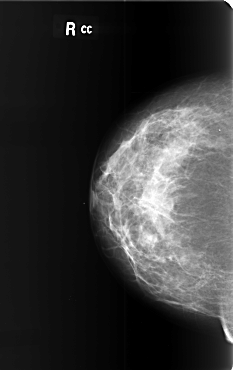

B_3400_1.RIGHT_CC

RIGHT_CC LINES 5912 PIXELS_PER_LINE 3720 BITS_PER_PIXEL 12 RESOLUTION 50 NON_OVERLAY